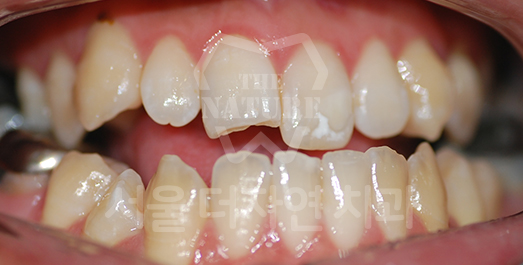

Impacted Tooth Solution

An impacted tooth remaining within the alveolar bone can cause damage to adjacent teeth. Orthodontic traction is used to guide the impacted tooth into its correct position,

allowing it to erupt and seat normally within the dental arch.

• BEFORE: 2011.08.12

• AFTER: 2013.07.08